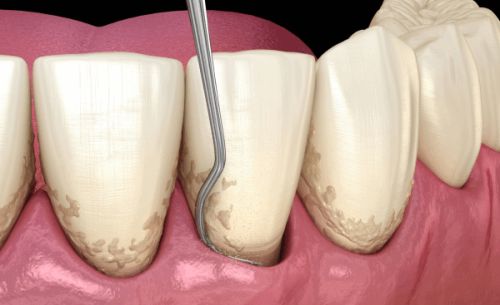

技术方面,成都新桥口腔目前注册医生200余名,其中包含多名华 西技术人才,他们不仅亲和力强,而且医术高明,能够根据患者的困扰快速找到问题所在,并制定出合理的方案进行治疗。尤其是对于种植牙和牙齿矫正项目,成都新桥口腔掌握有大量的临床成功数据,目前正畸实例3W +,种植牙实例10W +。除了常规的治疗技术外,他们也攻克了多项高难度手术,有牙齿问题的可以放心选择。收费上,作为一家有着多年经验的高品质牙科,成都新桥口腔在收费方面是严格按照卫生局标准执行的,收费公正合理透明,没有隐形消费,不用担心会有多收费或乱收费现象。

绝活上,在牙齿矫正和牙齿种植领域,新桥口腔在整个西部地区都是佼佼者,它是“隐适美”“时代天使”等大牌隐形矫正版牌以及“士卓曼”“诺贝尔”等高端种植体品牌的临床示范基地。医生团队上,新桥口腔有将近200名口腔医生,都是国内有名口腔院校毕业的精英,各个专科还有华 西口腔的骨干医生坐镇,技术水平完全不用担心。